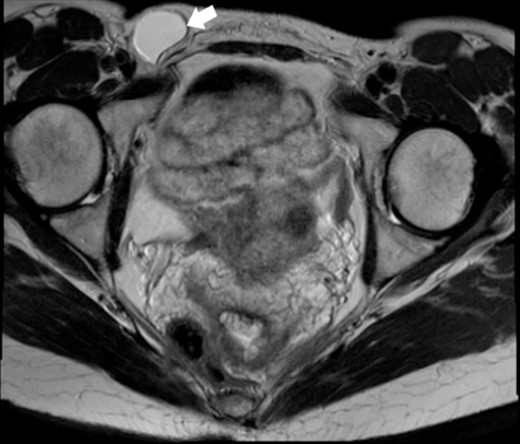

A 44-year-old Caucasian woman presented in our clinic with a painless swelling in the right inguinal region that appeared 10 months before her hospitalisation. A small soft mass measuring 4 × 2 cm2 was found on the physical examination. There were no changes in size or shape in the lesion when performing the Valsalva manoeuvre. Magnetic resonance imaging (MRI) showed an oval cyst measured 3.9/2.6/2.4 cm close to the uterus’s round ligament in the right inguinal channel. The lesion was hypointense in T1- (Fig. 1) and hyperintense in T2-sequence (Fig. 2). An anechoic cyst was observed using ultrasound. The cyst was classified as type I based on Counseller and Black’s classification [2]. Blood analysis showed no pathological changes.

MRI of the Cyst of the Canal of Nuck–T2 sequence. This figure displays the cyst (indicated by the white arrow), showcasing its appearance on a T2-weighted image.